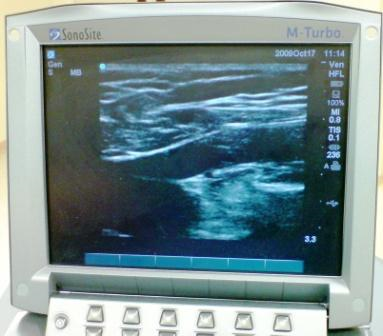

At your initial 30 min consultation the vascular surgeon who will perform a vein scan (doppler scan) to assess you further and decide the best way to treat your veins. This will involve putting some gel on your leg which can easily be washed off later. The surgeon will expose your whole leg from groin downwards to check your leg veins thoroughly. If you require a chaperone please let the doctor know.

Diagnosing which veins are faulty guides the vascular surgeon on how to treat the vein so this step is very important and is key to success of subsequent treatment. This scan is painless and is similar to scan in pregnancy. It does not involve X-rays.